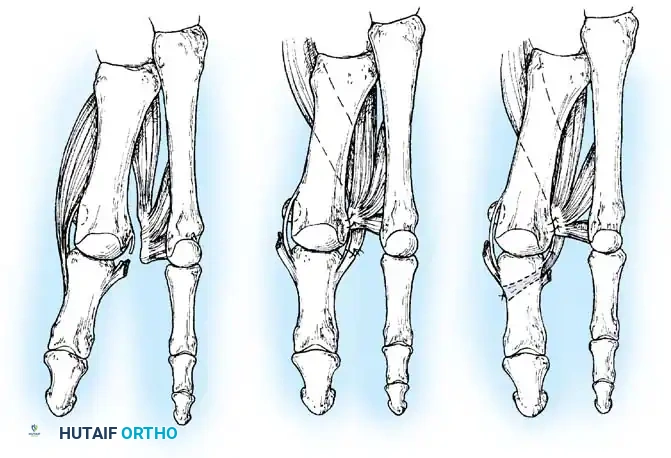

Hallux valgus (lateral deviation of the great toe) is not a single disorder, as the name implies, but a complex deformity of the fi rst ray that frequently is accompanied by deformity and symptoms in the lesser toes (Fig. 78-1). Often the angle between the fi rst and second metatarsals is more than the 8 to 9 degrees usually considered to be the upper limits of normal. The valgus angle of the fi rst metatarsophalangeal joint also is more than the 15 to 20 degrees considered to be the upper limits of normal (Fig. 78-2). If the valgus angle of the fi rst metatarsophalangeal joint exceeds 30 to 35 degrees, pronation of the great toe usually results. With this abnormal rotation, the abductor hallucis, which is normally plantar to the fl exion-extension axis of the fi rst metatarsophalangeal joint, moves further plantarward (Fig. 78-3). In this case, the only restraining medial structure is the medial capsular ligament with its capsulosesamoid portion (inserting into the base of the proximal phalanx) (Fig. 78-4) and capsulophalangeal portion (inserting into the plantar plate). The adductor hallucis, which is unopposed by the abductor hallucis, pulls the great toe further into valgus, stretching the medial capsular ligament (particularly the capsulosesamoid), attenuating this structure, and allowing the metatarsal head to drift medially from the sesamoids. In addition, the fl exor hallucis brevis, fl exor hallucis longus, adductor hallucis, and extensor hallucis longus increase the valgus moment at the metatarsophalangeal joint, further deforming the fi rst ray. The deep transverse intermetatarsal ligament runs between the plantar plates at the metatarsophalangeal joints and does not insert into bone on the adjacent sides of the metatarsal heads. Finally, the sesamoid ridge on the plantar surface of the fi rst metatarsal head (the crista) fl attens because of pressure (abutment) from the tibial sesamoid (Fig. 78-5). With this restraint lost, the fi bular sesamoid displaces partially or completely into the fi rst intermetatarsal space (see Fig. 78-2). In this situation, the patient is bearing less weight on the fi rst ray and more on the lesser metatarsal heads, increasing the likelihood of transfer metatarsalgia, callosities, and stress fracture of a lesser metatarsal.

Fig. 78-3 Pronation of hallux. A, Normal. B, Note plantar shift of abductor hallucis and lateral shift of sesamoids with associated intrinsic muscles of hallux. (Redrawn from Miller J: Acquired hallux varus a preventable and correctable disorder, J Bone Joint Surg 57A:183, 1975.)

Fig. 78-5 A, Plantar surface of fi rst metatarsal head. Entire sesamoid sling with attached intrinsic musculature has been rotated distally off metatarsal head to present schematically relationships of muscle, tendon, capsule, ligaments, and articular confi guration of fi rst metatarsophalangeal joint. B, As metatarsal head moves medially, sesamoid sling apparatus becomes valgus deforming force, and metatarsal rotates (pronates) on its longitudinal axis. Intrinsic and extrinsic muscle balance is lost, and deformity increases. ( A after Beverly Kessler; courtesy of LTI Medica and The Upjohn Company.)